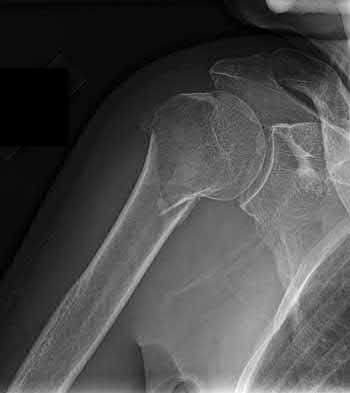

2. # A 35-year-old woman is involved in a head-on collision while driving. Initial radiographs are shown in Figures 8a and 8b. Injury to what vessel increases the risk for osteonecrosis of the injured bone?

1. Dorsalis pedis artery

2. Perforating peroneal artery

3. Lateral tarsal artery

4. Artery of the tarsal canal

5. Artery of the tarsal sinus Corrent answer: 4

The patient has a Hawkins type III talar neck fracture-dislocation with a risk of osteonecrosis ranging from 69% to 100%. Anatomic studies have shown that the artery of the tarsal canal supplies the lateral two thirds of the talar body.

The other vessels listed provide no significant contribution to the talus.